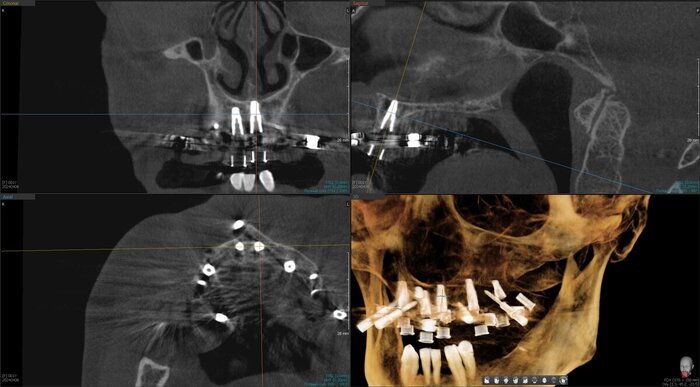

Получилось так, что сверху всего 8 зубов, по 4 с каждой стороны. Чёрная точка (которую вы точно увидите, скос эмали на зубе 1.1) - конструктивные особенности, всё это будет закрыто пломбировочным материалом. Зуб 1.1 - дополнительный имлантат, который потом планируем убрать. Он нужен лишь для усиления, ибо торк полноценный был получен только на одном из остальных 6-ти установленных.

Напоминаю - протезы временные адаптационные

Так же важный момент - верхний протез соприкасается с нижним только в точках полученного торка (их всего 2), остальное "на весу" и жевать не способно.

Рекомендации - мягкая, жидкая пища 4 месяца! Это важно.

Низ - всё ок.